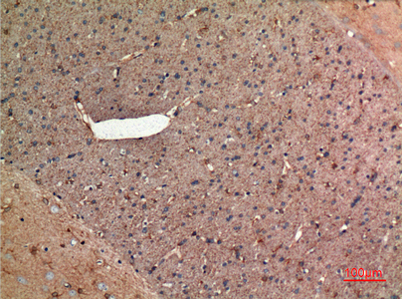

| Dilutions: | Western Blot: 1/500 - 1/2000. IHC-p: 1:100-300 ELISA: 1/20000. Not yet tested in other applications. |